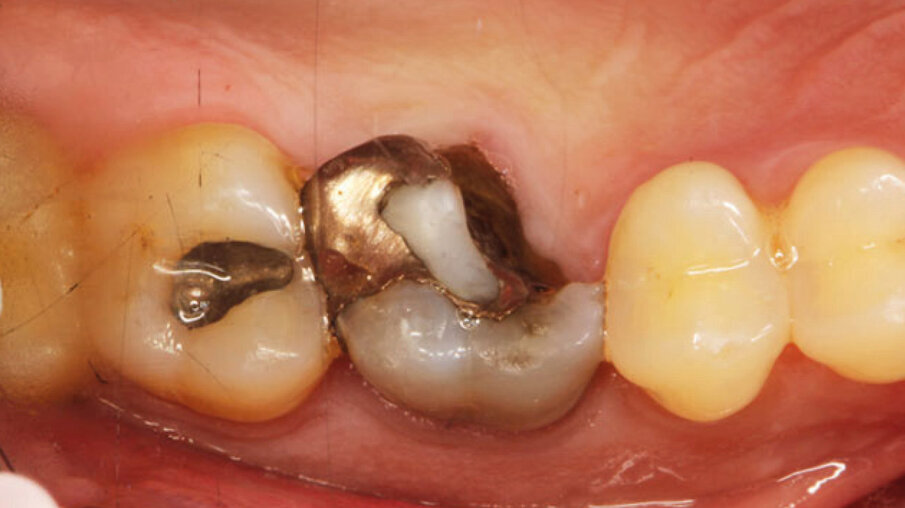

Dopo l’esecuzione dell’anestesia locale, il dente è stato rimosso e l’alveolo pulito dai residui del legamento parodontale. È stato inserito l’impianto (Zimmer TSV, Zimmer, Parsippany) 4.1 x 11,5 TSVM posizionato seguendo il protocollo consigliato dal produttore (Fig. 3). L’impianto è stato inserito a livello della cresta alveolare. È stato avvitato lo scan-abutment (Zfx Intrascan Matchholder, Zfx,). È stata rilevata un’impronta ottica intra-operatoria dell’emiarcata in cui è stato posizionato l’impianto con lo scan abutment (Fig. 3). Il gap tra l’osso vestibolare e l’impianto è stato riempito con Bio-Oss (Geistlich Pharma) (Fig. 4). Al termine della chirurgia è stato progettato e fresato il provvisorio, che è stato applicato appena pronto, dopo aver inserito la matrice in collagene volumetricamente stabile Fibro-Gide (Geistlich Pharma) precedentemente imbibita con il gel a base di polinucleotidi e acido ialuronico Regenfast (Officine Bio-Farmaceutiche Mastelli), al di sotto della vite stessa (Figg. 5, 6). Data l’accuratezza della vite non sono state necessarie suture. Al termine della procedura è stata eseguita una radiografia di controllo (Fig. 7).

Fig. 6_Vite customizzata in situ con interposta la matrice in collagene Fibro-Gide, precedentemente imbibita di gel Regenfast.